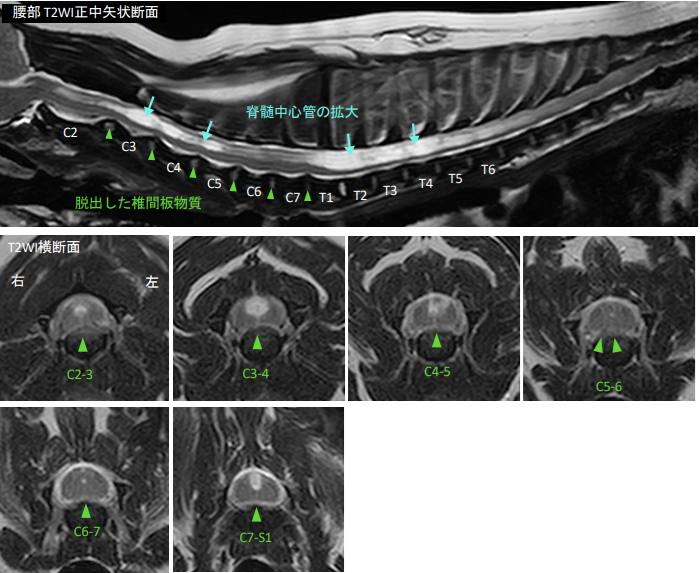

首周りの痛みを訴える疾患は多岐にわたり、レントゲンやCTなどを併せることで骨格に関する異常などがないかや椎間板ヘルニア以外の疾患を併発していないかなどを調べることで診断の精度が高くなります。最終的にはMRI検査により神経組織への圧迫部位や程度を確認し確定診断となります。

↑頸部に多発性の椎間板ヘルニアが認められる